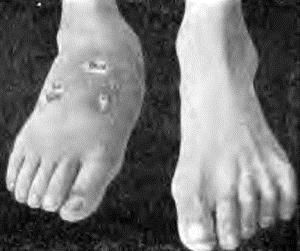

- В області уражених кісток або суглобів помітні припухлості, рясні виділення серозного ексудату, атрофія м'яких тканин,

- Укорочення кінцівок, сильне м'язове виснаження і утворення численних гнійників.